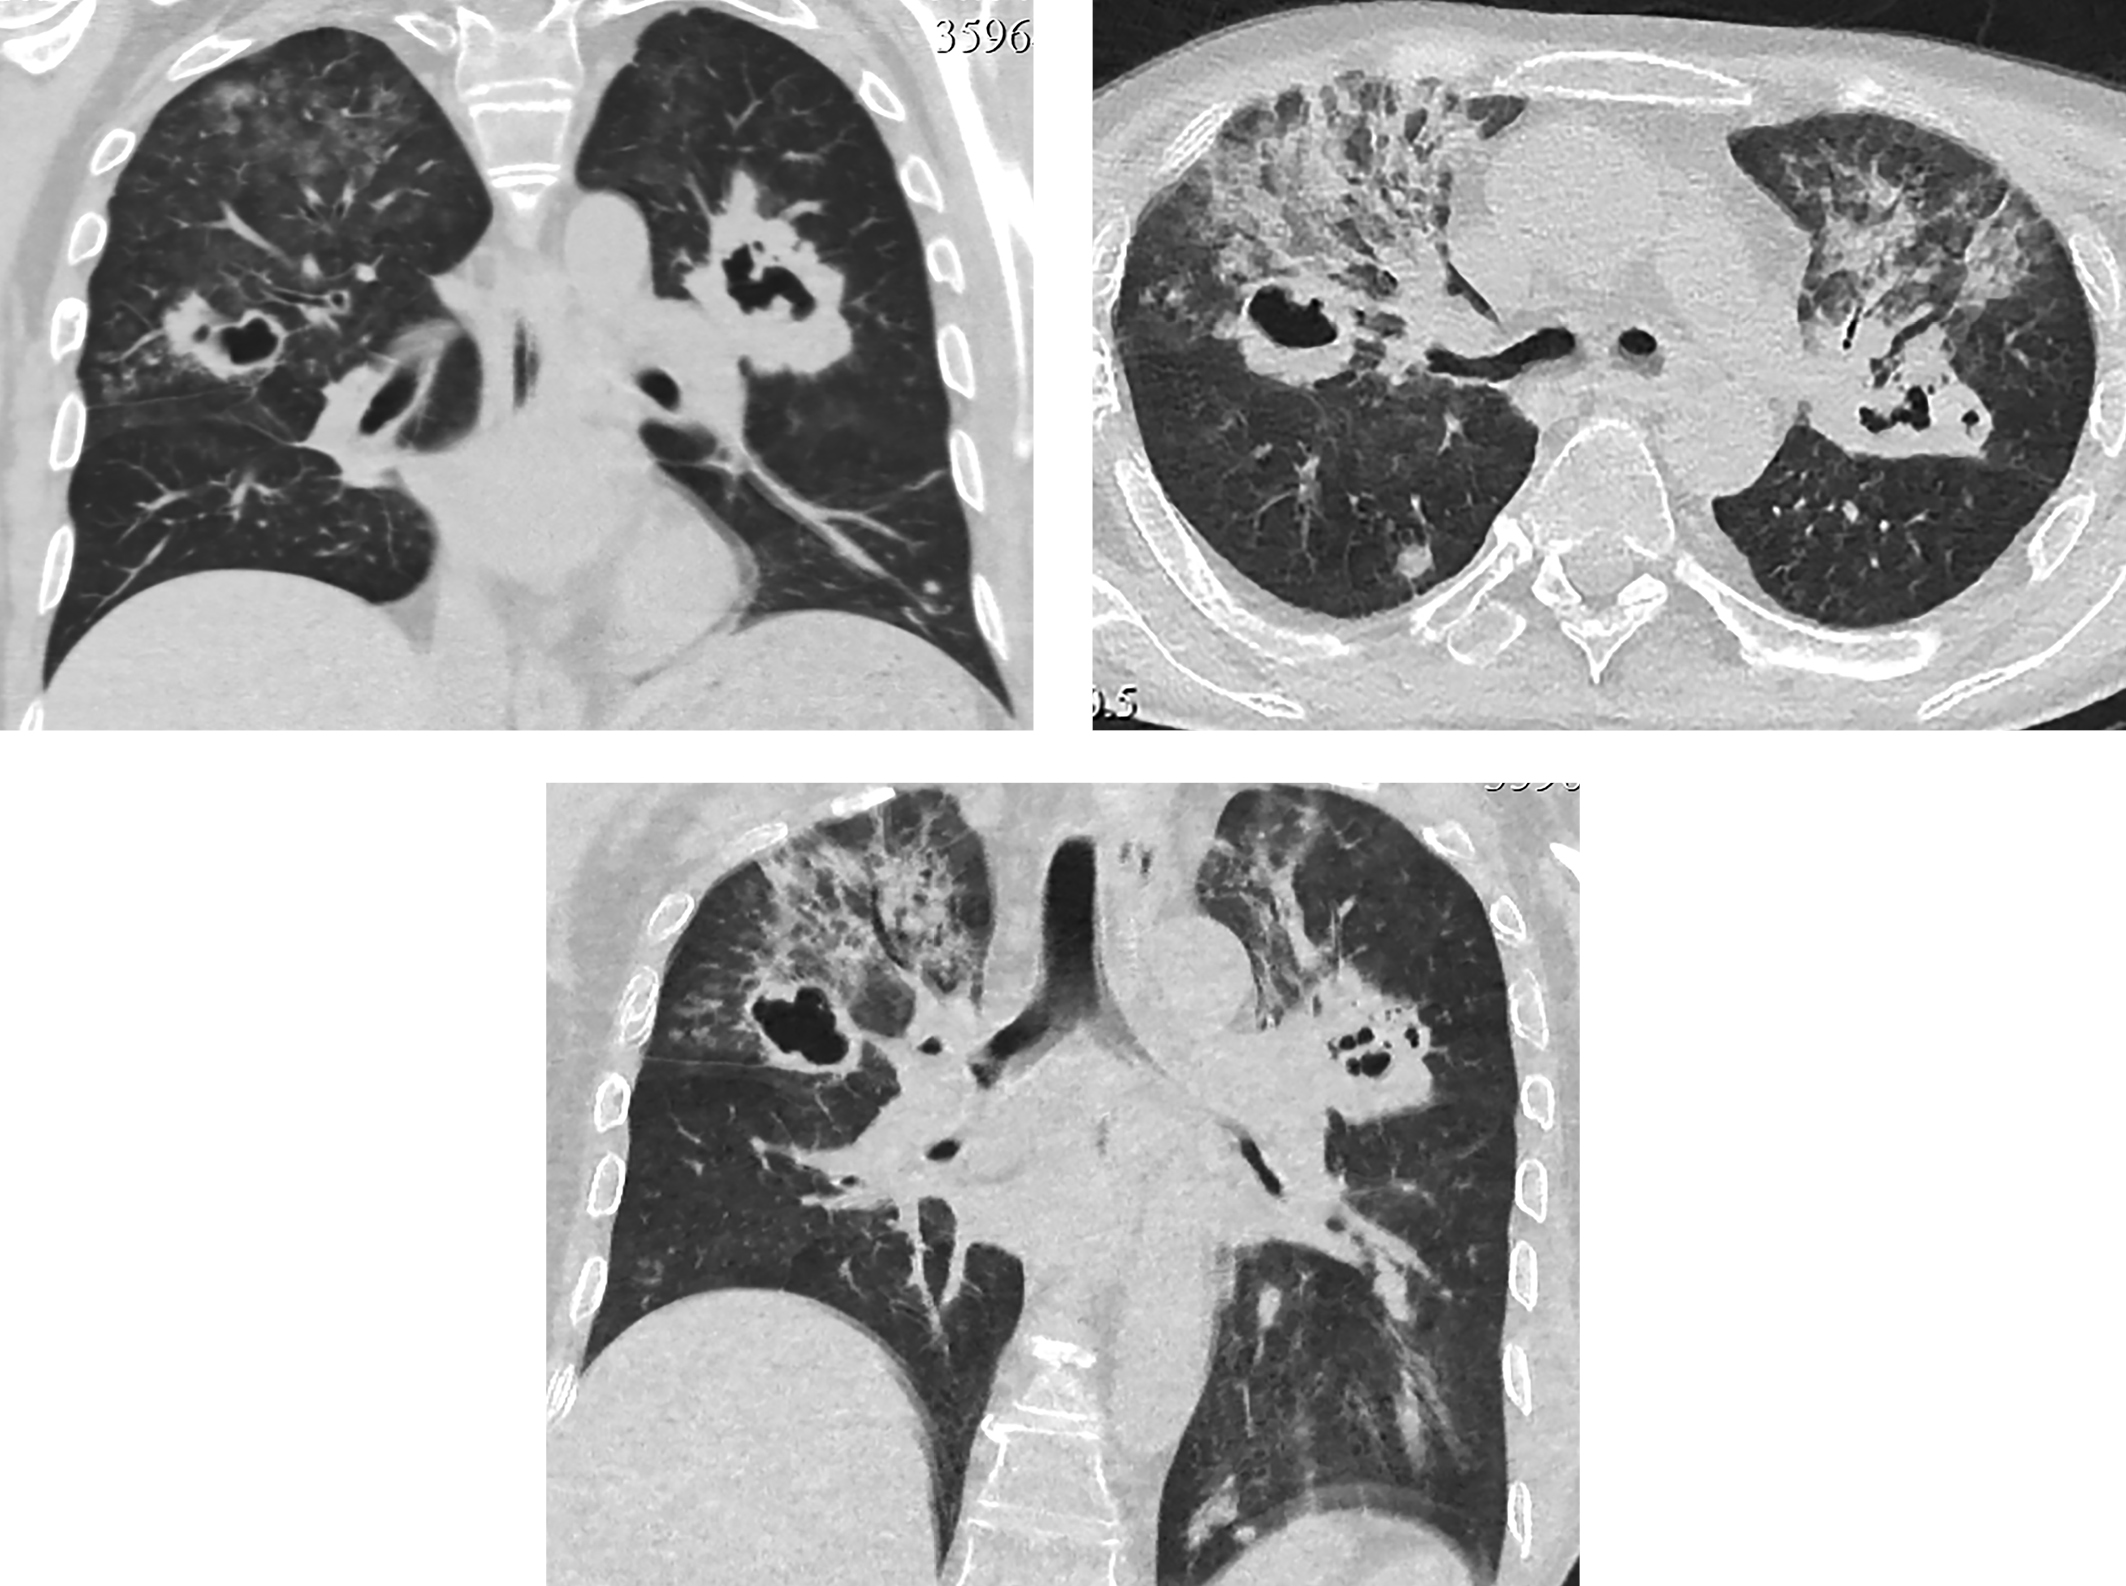

Через 5 дней после операции при контрольной КТ грудной клетки в обоих легких визуализированы множественные шаровидные образования с признаками распада по типу абсцедирования, размером до 4,2 см (рис. 7). Рассеянные очаговые образования в обоих легких до 1 см; в S9,10 левого легкого пневмоническая инфильтрация легочной ткани по типу консолидации; в верхних долях диффузная очаговая интерстициальная инфильтрация.

Рисунок 7. Контроль КТ грудной клетки через 5 дней после операции: в обоих легких множественные шаровидные образования с абсцедированием до 4,2 см. Рассеянные очаговые образования в обоих легких до 10 мм. В S9,10 левого легкого пневмоническая инфильтрация.